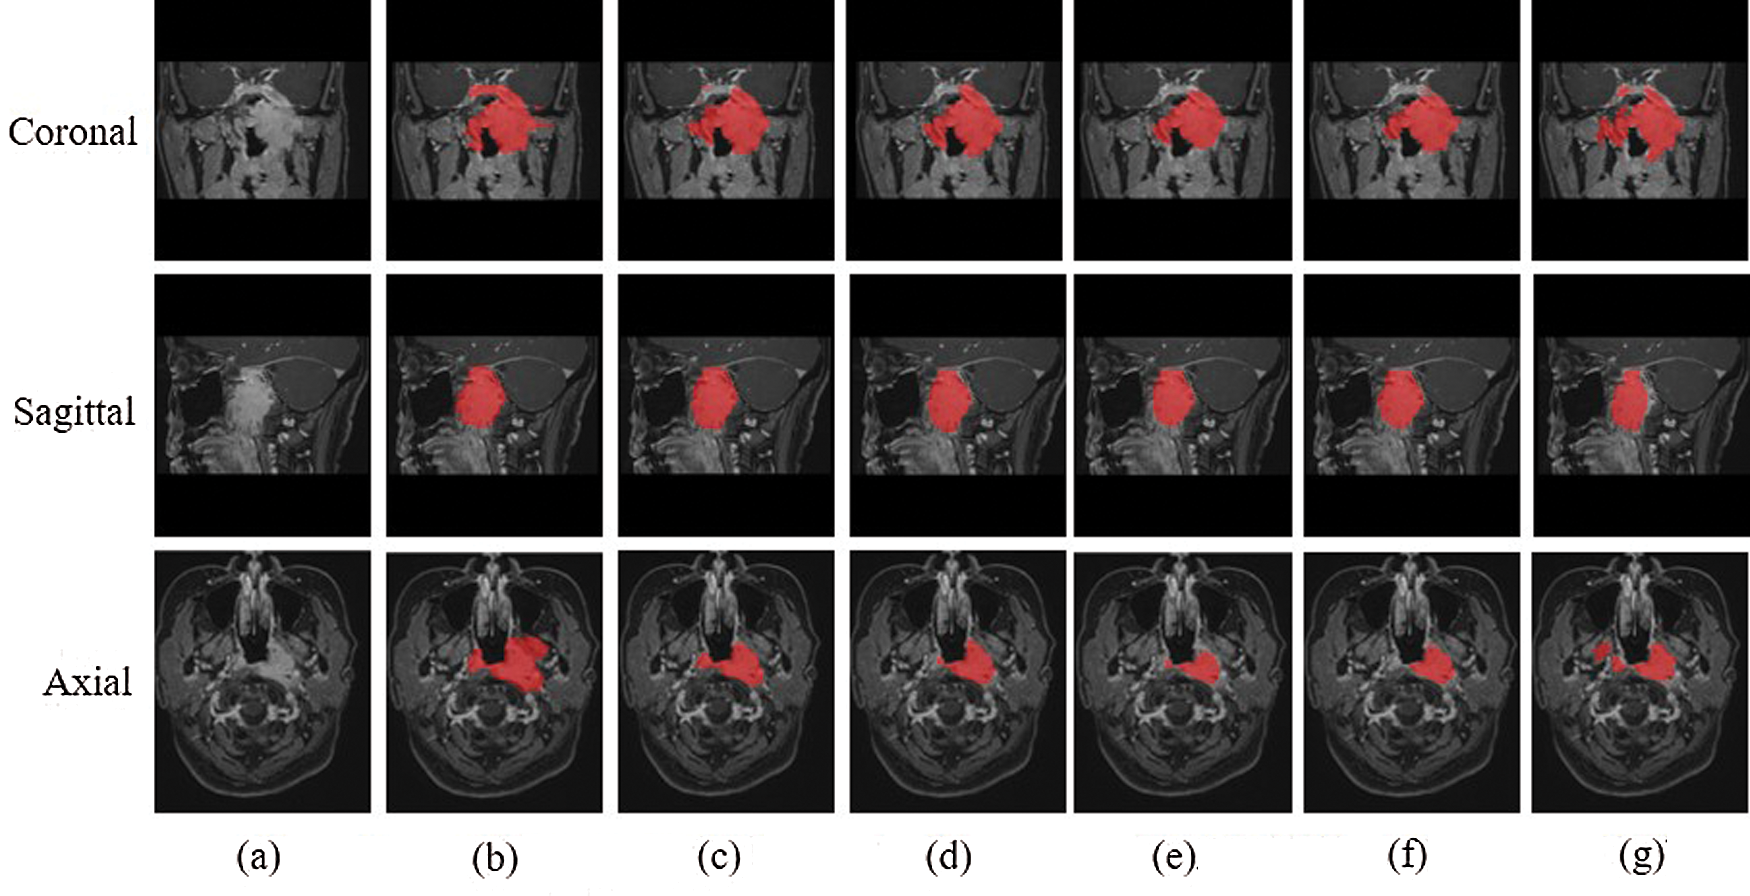

The experimental results were evaluated qualitatively and quantitatively. Fig. 7 shows the two-dimensional segmentation results of different network structures on the same dataset in the experiment. Each row is the segmentation result of the same patient, showing 3 patients in total. Fig. 8 shows the 3D segmentation results of different network structures on the same dataset. It shows the coronal, sagittal, and axial segmentation results for the same patient.

Figure 7: 2D segmentation graphs of different network structures on the same dataset (a) Raw (b) Ground truth (c) CSCN (d) CNN (e) ACDNet (f) Deeplab (g) V-Net

Figure 8: 3D segmentation graphs of different network structures on the same dataset (a) Raw (b) Ground truth (c) CSCN (d) CNN (e) ACDNet (f) Deeplab (g) V-Net

It can be seen from the figure that the segmentation effect of V-Net is not good. Its segmentation result is quite different from the Ground truth, which is not suitable for the segmentation of NPC images. The sagittal segmentation results of various methods are good, which are close to the Ground truth. In the coronal and axial segmentation, the method presented in this paper has the best performance.